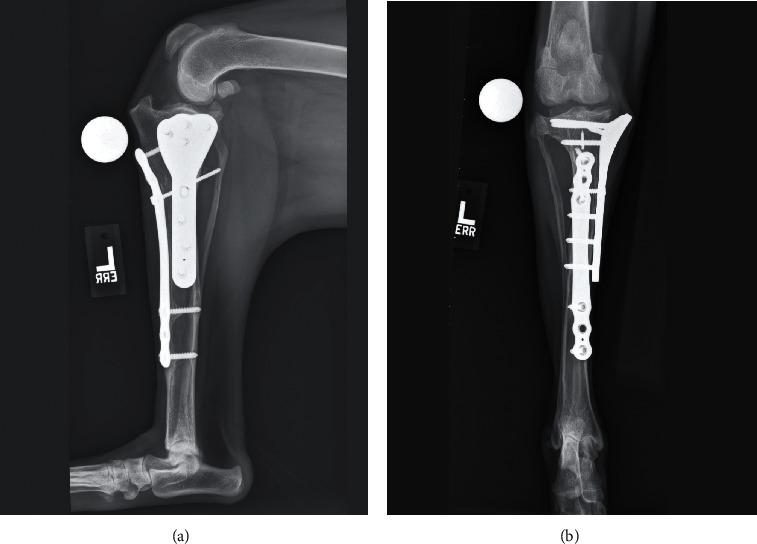

A 9-month-old mixed-breed dog was presented for bilateral proximal tibial deformity resulting in an excessive tibial plateau angle and cranial cruciate ligament insufficiency. Initial surgical management of the right pelvic limb was done by performing a cranial closing wedge ostectomy. Inadequate leveling of the plateau resulted in a postliminal meniscal tear which was addressed during a revision tibial plateau leveling osteotomy. The left pelvic limb was managed in a single-session surgery using three-dimensional (3D) virtual surgical planning and custom 3D-printed surgical guides to perform a combined cranial closing wedge ostectomy and tibial plateau leveling osteotomy. Postoperative 3D analysis of the left tibia revealed the accuracy of the surgical result within 2° of the virtual surgical plan. The dog developed a transient grade II/IV left medial patellar luxation following surgery but ultimately attained a full functional recovery and was actively engaged in competitive agility work 46 months following surgery on the left pelvic limb.

一只9个月大的混血犬因双侧胫骨近端畸形导致胫骨平台角过大和颅侧交叉韧带功能不全前来就诊。右后肢最初的手术治疗是通过进行颅侧闭合楔形截骨术。由于平台平整不足导致术后半月板撕裂,在翻修胫骨平台平整截骨术时进行了处理。左后肢采用单阶段手术,使用三维(3D)虚拟手术规划和定制的3D打印手术导板,进行联合颅侧闭合楔形截骨术和胫骨平台平整截骨术。术后对左胫骨的3D分析显示,手术结果的准确性在虚拟手术计划的2°范围内。这只狗术后出现了短暂的左侧髌骨二级/四级脱位,但最终完全恢复了功能,在左后肢手术后46个月积极参加了竞技敏捷运动。